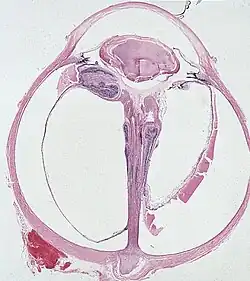

| Falciform fold of detached dysplastic retina encircles the persistent hyaloid artery that extends from the optic nerve head to the retrolental mass. | |